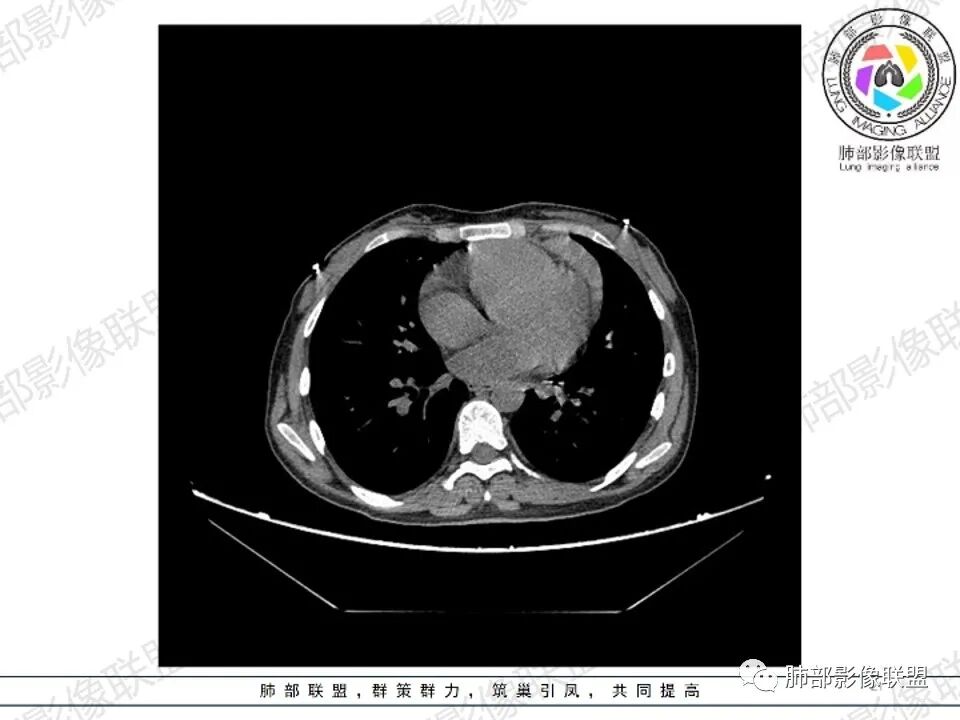

2.影像显示前纵隔不规则块状影,依势贴附心脏大血管旁,密度不均,边界不甚清楚,有结节融合感。

3.病灶轻度不均匀强化,可见血管穿行,散在液性低密度区。

双肺门未见肿大淋巴结。

4.双侧腋窝区见增大淋巴结,边界清楚。